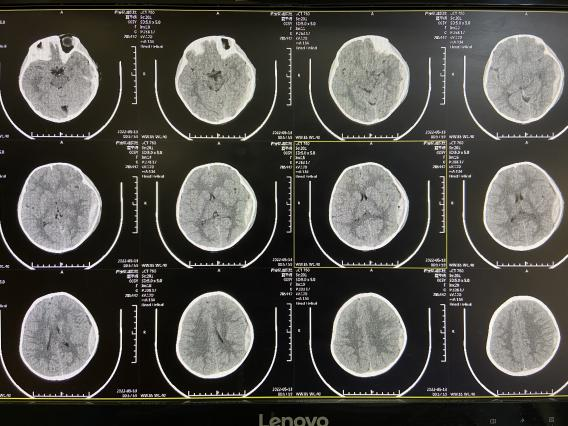

5月13日凌晨接急诊科电话,一个5岁女孩从床上摔倒在地,头痛伴恶心来诊。急诊行头颅CT示:左侧颞枕部硬脑膜外血肿,左侧颞骨骨折。患儿精神欠佳。

(入院时CT图片)

陈斌主任第一时间阅览CT及患者症状和体征、向患儿家属告知患儿病情,患者外伤,密切观察患儿情况,6小时后复查头颅CT提示:出血量较前增加,且部分脑组织受压,患儿精神状态加重;再次向患者家属告知病情后建议手术治疗。患者家属犹豫不决,担心开颅手术风险。

(6小时后复查CT)

手术长达2小时,术中陈斌主任反复查看术区,并将颅骨复位,最后美容缝合皮肤;手术顺利,术后患者清醒。术后复查头颅CT如下图。

(术后第一天复查)